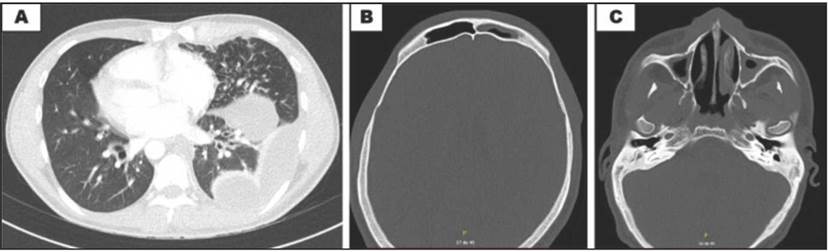

Figura 2 A: tomografía de tórax, plano axial, con derrame pleural izquierdo, engrosamiento peribronquial y bronquiectasias bilaterales, algunas con tapón mucoso. B: tomografía de senos paranasales, muestra sinusitis frontal. C: etmoidal y maxilar bilateral.